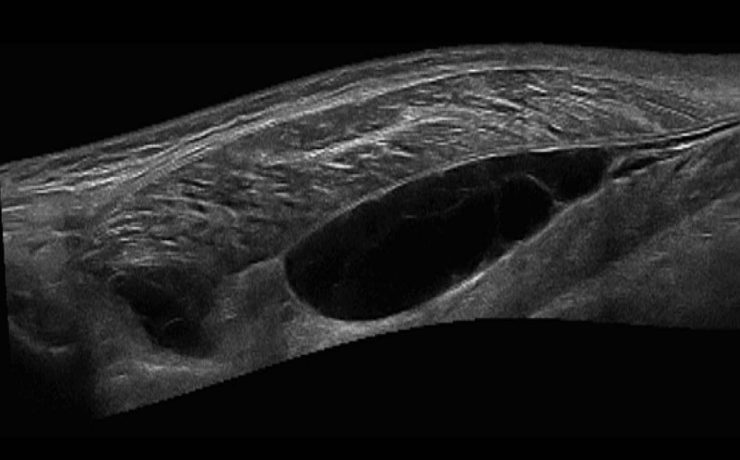

Revista Anales de Radiología de México. Ultrasonido Tiroideo en pacientes dediatricos del HIM, con diagnostico clínico de Tiroiditis de Hashimoto. México 2012 (11) – 1. Se revisaron 64 pacientes, por US más frecuente en mueres 9/1, y la lesión común es nódulo único, hipoecogénico, con contenido sólido, con vascularidad periférica.